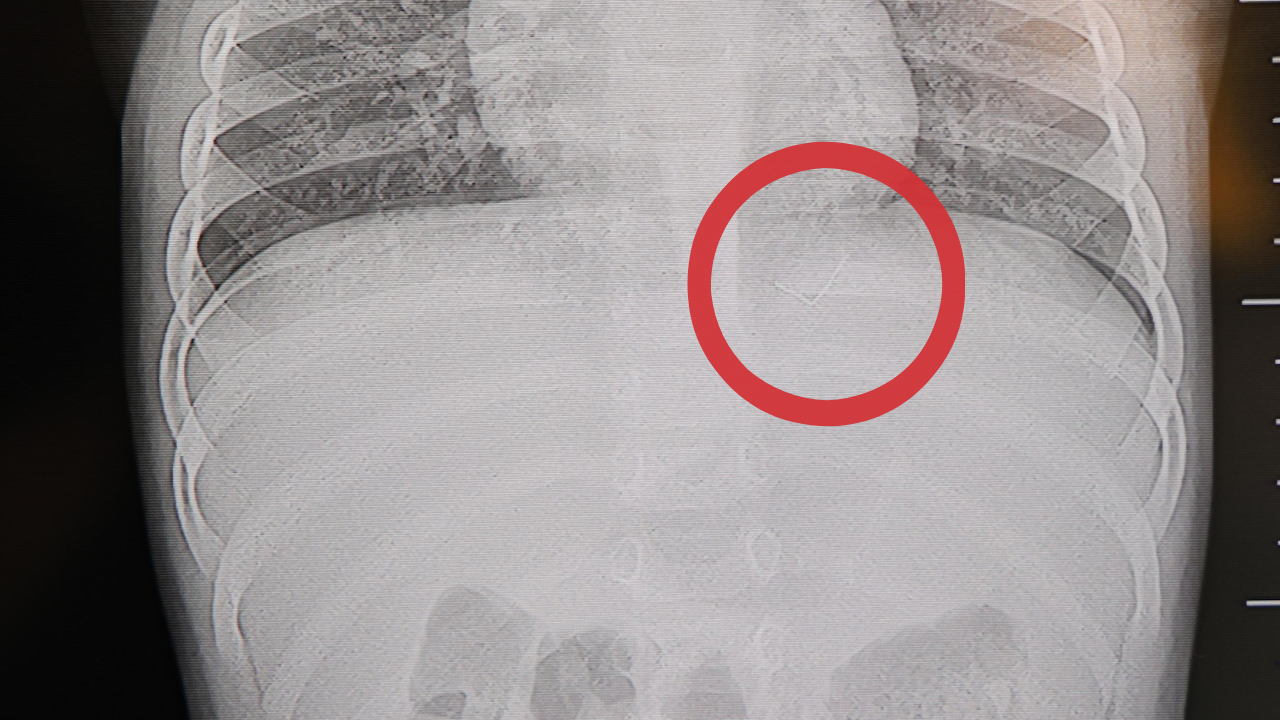

Çocuklarının acı çekmesine dayanamayan aile, son olarak özel bir hastaneye başvurdu. Burada Beyin ve Sinir Cerrahisi Uzmanı Prof. Dr. İdris Altun tarafından yapılan detaylı tetkiklerde korkunç gerçek ortaya çıktı. Bebeğin sırtındaki yabancı cismin cilt altında olduğu, omurilik kanalına çok yakın durduğu ve hareket ederek akciğer zarına doğru ilerlediği tespit edildi.

Durumun ciddiyeti üzerine Prof. Dr. Altun, bebeği genel anesteziyle tamamen uyutmak yerine, lokal anestezi ve sedasyon (sakinleştirme) yöntemiyle ameliyata aldı. Başarılı geçen operasyonla, bölgedeki 2 santimetre uzunluğundaki ince zımba teli benzeri metal cisim çıkarıldı. Bebek aynı gün sağlığına kavuşarak taburcu edildi.

"Sırtında yabancı bir cisim olduğu söylenmiş ancak çıkarılamayacağı ve 8 yaşına kadar beklenmesi gerektiği ifade edilmişti. Bize başvurduğunda yaptığımız tetkiklerde, cilt altında, omurilik kanalına çok yakın ve akciğer zarına doğru ilerleyen bir yabancı cisim tespit ettik. Hastamızı tamamen uyutmadan, lokal anestezi ve sedasyon eşliğinde müdahale ederek lezyonu tamamen çıkardık. Çıkardığımız cismin ince zımba teline benzer, yaklaşık 2 santimetre uzunluğunda metal bir tel olduğunu gördük. Bu yabancı cisim alınmasaydı, bölgede enfeksiyon gelişebilirdi. Enfeksiyon sonucu omurilik kanalında ciddi hasarlar oluşabilir, çocuk büyüdükçe cismin hareket etmesine bağlı olarak omurilikte zedelenmeler meydana gelebilirdi. Ayrıca yana doğru ilerleyerek akciğer zarına ve akciğere batma riski vardı. Bu da enfeksiyona ve ilerleyen süreçte tümörle karışabilecek tablolara neden olabilirdi. Şu an hastamız gayet sağlıklı. Gerekli kontrolleri yaptık ve aynı gün taburcu ettik" dedi.